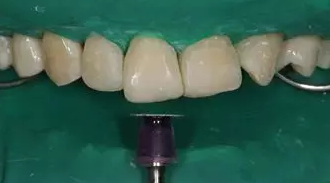

病例分享|復(fù)合樹脂微創(chuàng)美學(xué)修復(fù)關(guān)閉上前牙間隙

修形,拋光